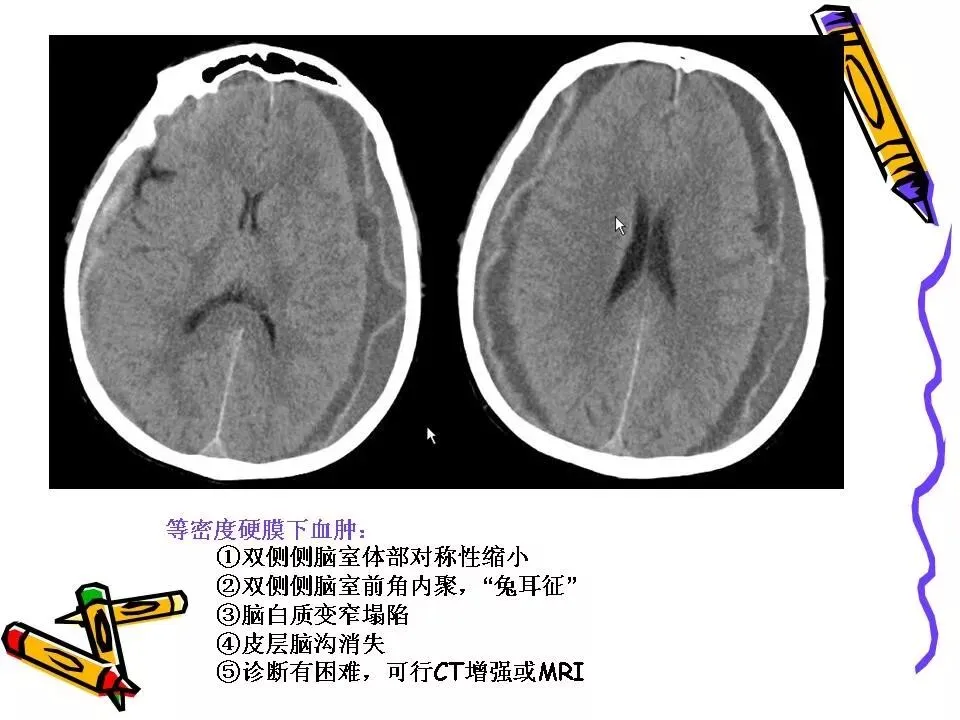

>常见颅脑外伤CT诊断(PPT)

常见颅脑外伤CT诊断(PPT)